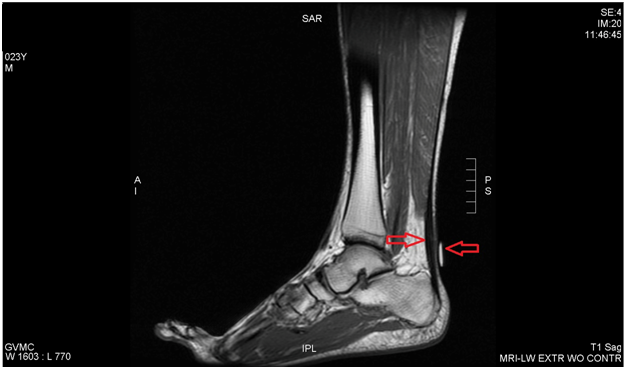

We report a case of Achilles tendinosis that was treated with a high volume, hydrodissection visualized by conventional B-mode ultrasound. Prior MRI revealed a thickened right Achilles tendon with a small defect. Ultrasound examination showed a thickened Achilles tendon with physical exam revealing a prominent Haglund’s deformity, mild fusiform swelling and pain along the posterior Achilles (Figure 1 & 2). The condition had been poorly responsive to standard management including protected ambulation in a cam walker boot, anti-inflammatory medication, modalities and therapeutic exercise, as well as a platelet rich plasma injection. We suggest using high volume ultrasound guided injection adjacent to (anterior to) the Achilles tendon as an adjunct to treat this difficult clinical syndrome.

Figure 2 T1, sagittal imaging shows prominent Haglund’s deformity and fusiform swelling.